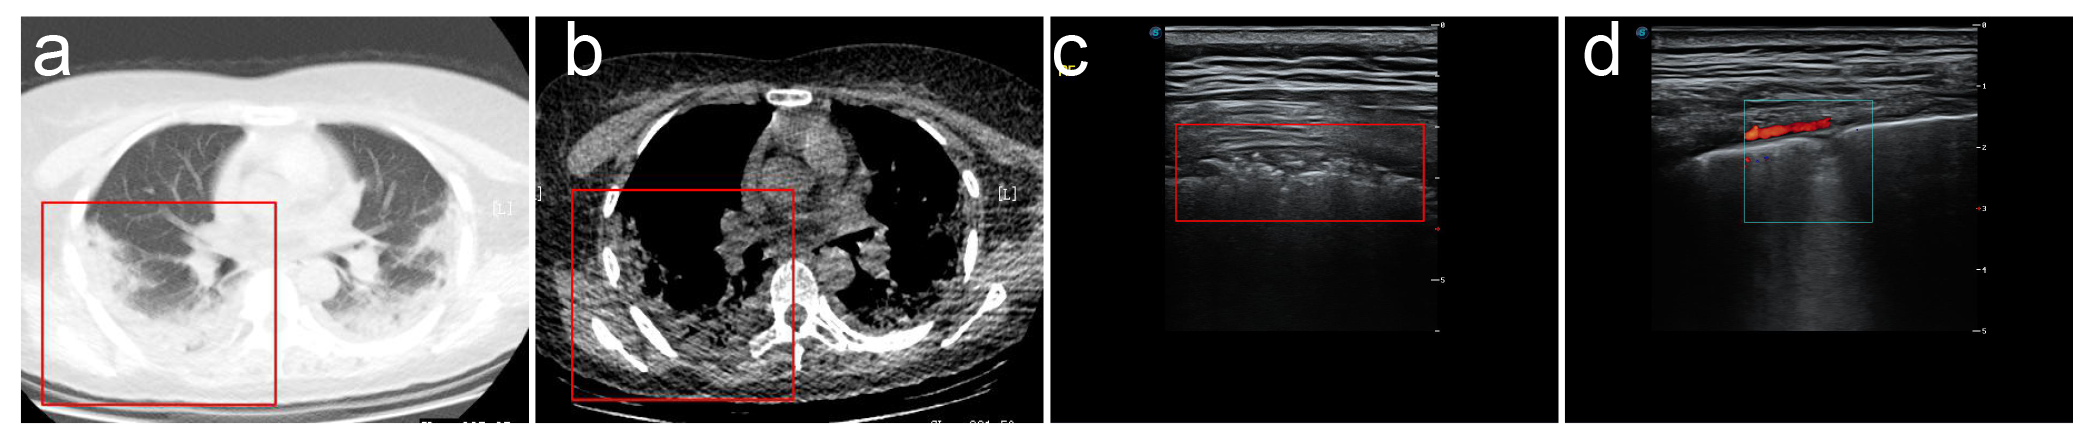

主要观察内容:(1)胸膜线是否光滑、连续是否中断;(2)双肺肺周"B"线分布位置,数目,是否融合;(3)如有肺周病灶应观察病变回声、部位、形态、范围;(4)如有实变观察其内是否有支气管充气征,或细支气管肺泡充气征;(5)应用彩色多普勒超声技术了解实变肺部病灶血流分布等;(6)胸膜下病灶周围是否出现胸腔积液,胸膜是否出现局限性增厚,有无胸腔积液。

6.高频超声还可显示病变肺周的胸膜局限性增厚及胸膜下病变周围局限胸腔积液(线阵探头更清晰多数患者胸膜增厚约1-2mm,病灶周胸腔内局限性胸膜下积液约2-3mm)随病情进程有所变化。

7. CDFI超声显示非重症期新型冠状病毒肺炎(COVID-19)患者胸膜下实变病灶血流信号不敏感,随更换多台不同品牌新型超声仪器仍显示呈乏血流表现,具体原因可能与病变的病理性质有关,同时与病变进展时期有关,但应引起高度重视,因普通炎症所致肺实变彩色多普勒超声显示呈丰富血流信号,一般预后较好但新型冠状病毒肺炎(COVID-19)患者病变一般进展迅速,引起患者死亡,是否与肺组织未能迅速建立起丰富微小血管交换机制相关还有待于进一步研究,但值得肯定的是彩色多普勒超声相比其他医疗设备更能有效直观的了解实变肺组织血供信息,对临床医生预先判断患者预后及病情进程有重要的临床价值。